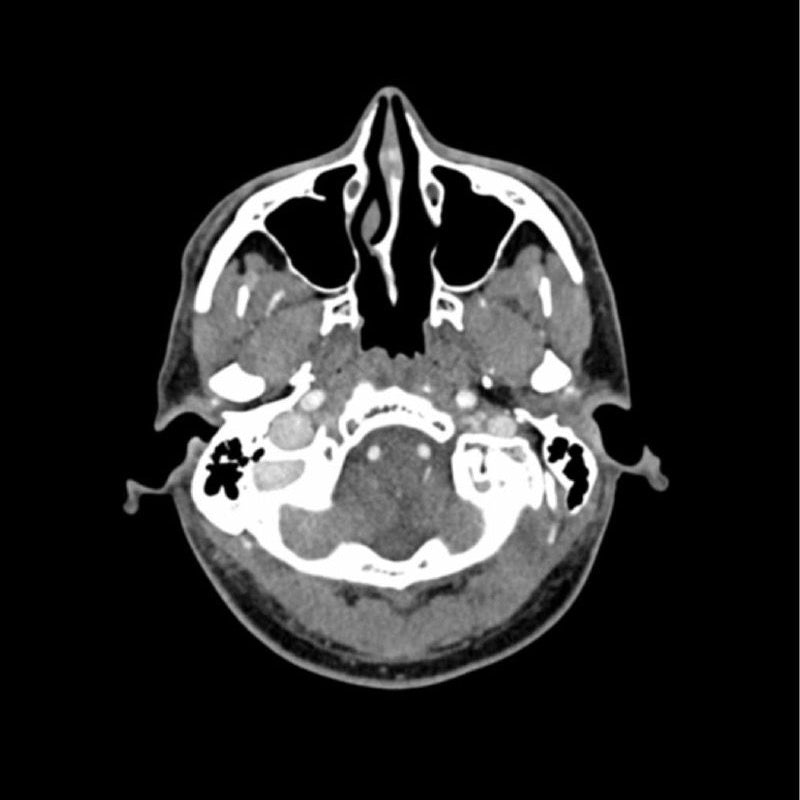

This phantom simulates a contrast medium enhanced head in arterial phase (CT angiography). It covers the vertex to the foramen magnum. The phantom has 10 low-contrast lesions in the centrum semiovale and the right hemisphere has an arteriovenous malformation.

The phantom can be used in CT (including CBCT) to evaluate and optimize imaging performance and AI-enabled diagnosis. It is also suited for training purposes. The phantom provides a detailed and realistic simulation of vascular structures, soft and bone tissue. Air voids are filled with a cellulose-polymer composite of approx. -160 HU.

- Realistic simulation of head vessels, bone and soft tissues.